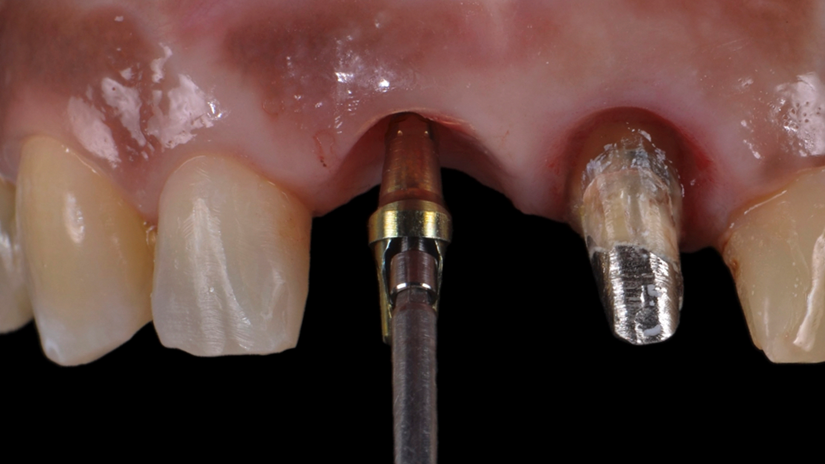

A paciente apresentava queixas estéticas e funcionais. Após avaliação clínica e radiográfica, optou-se pela substituição do pilar reto por um pilar Ideale angulado de 17 graus e 3,3 mm de diâmetro. Esse componente mais estreito e angulado permitiu corrigir o eixo emergente da futura coroa, viabilizando o planejamento de uma prótese parafusada na região estética.

O caso foi conduzido com planejamento cuidadoso, moldagens analógicas e provas clínicas. A reabilitação foi finalizada com a instalação de uma coroa metalocerâmica parafusada, garantindo estética, funcionalidade e reversibilidade do conjunto protético.